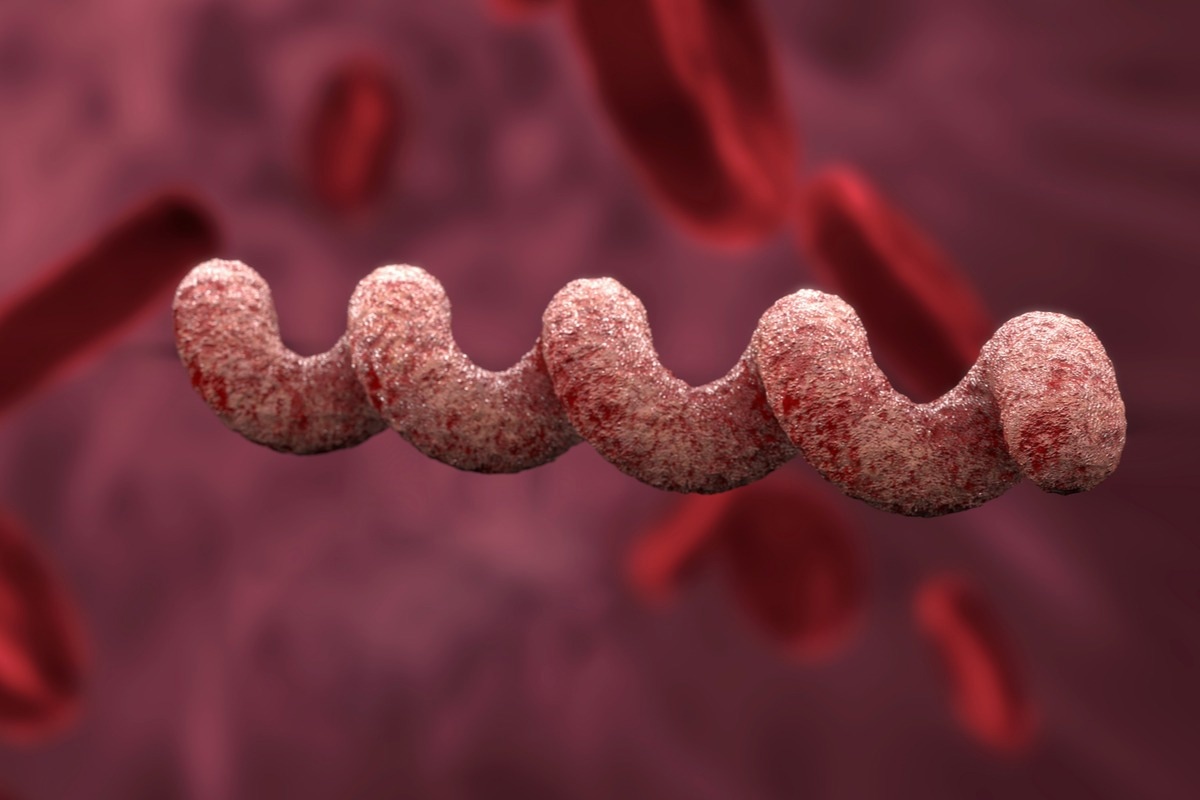

Лептоспиры: фотографии удивительных микроорганизмов